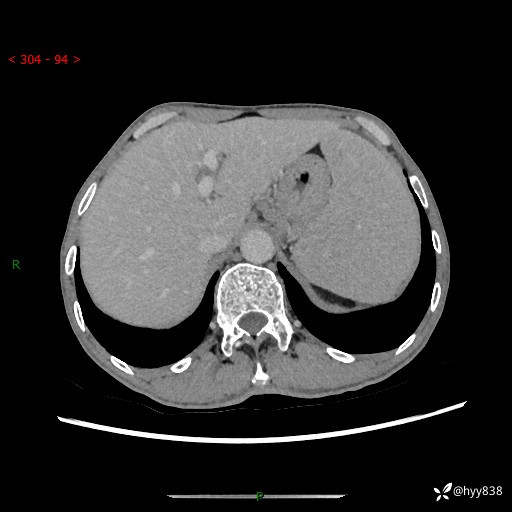

老年男性,脾大并脾脏弥漫粟粒状低密度,淋巴瘤 VS 肉芽肿 VS 血管瘤---结果公布

简要病史: 患者于3月前无明显诱因出现脾大,伴腹部轻微不适,具体不详,无腹痛、腹泻、腹胀,无头晕、头痛、乏力,无恶心、呕吐、呕血,无胸闷、气短、胸痛不适

上腹部CT平扫+增强